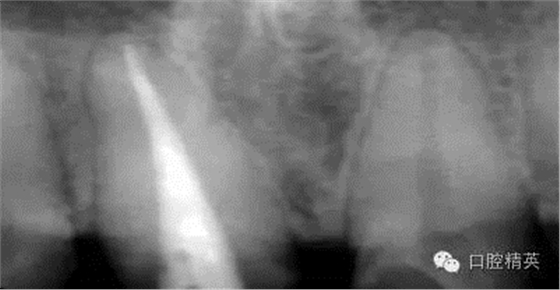

根管治療更是牙體修復(fù)的基礎(chǔ),根據(jù)術(shù)前診斷,對(duì)需要做根管治療的或有必要重新做根管治療的,一定要做到恰充,消除隱患,避免將來冠修復(fù)好后,出現(xiàn)根尖炎癥的問題(見圖3、4、5)。在基礎(chǔ)工作做好后,接下來開始牙體預(yù)備,根據(jù)跟個(gè)人習(xí)慣,選擇合適的車針(圖6、7)。